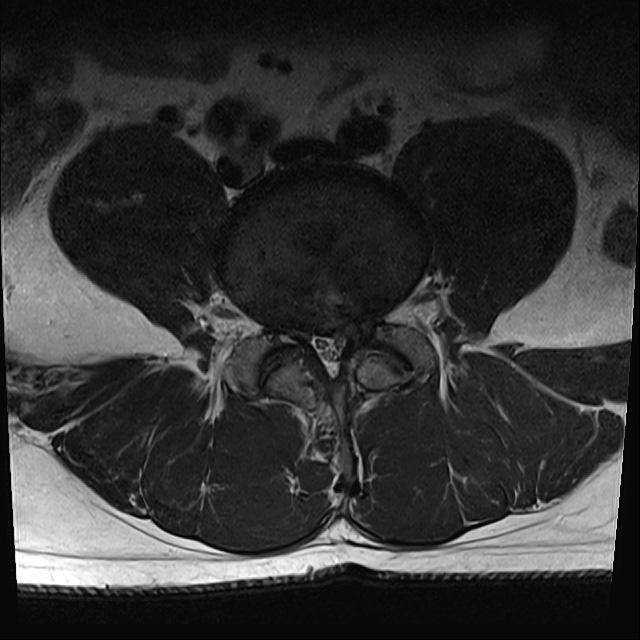

L4-5번 후궁절제술 경험이 있습니다. 근전도 검사에서 신경근병증 받았구요..재발인거 같아 수술고려중인데 판독부탁드립니다.감사합니다;).

• 1번 째 사진